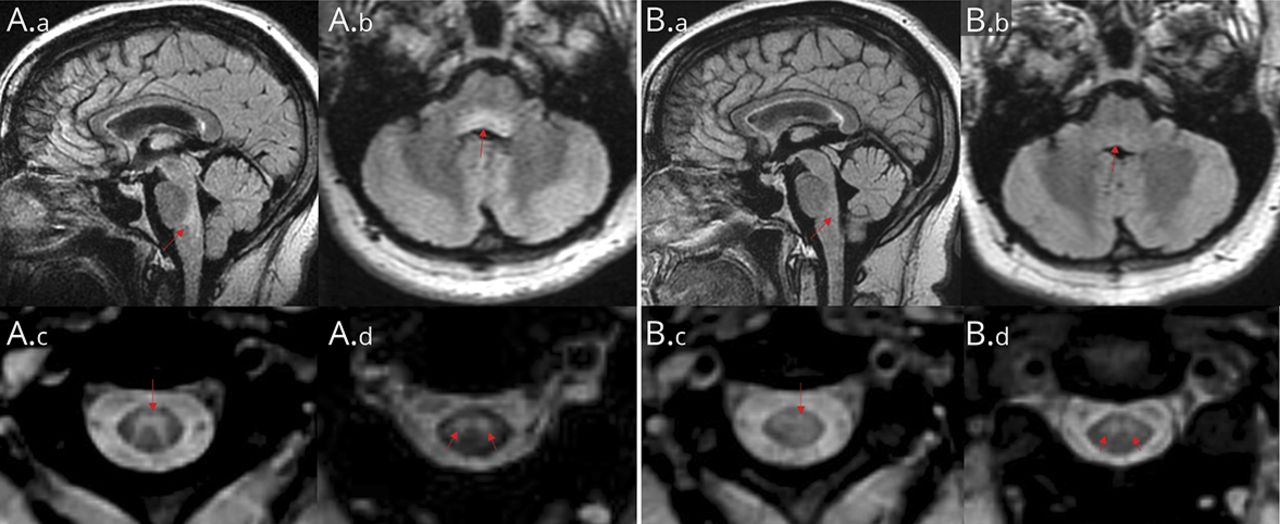

MRI显示脑桥背侧及髓质有高t2加权信号(图1A.a、A.b)及上颈髓,主要累及中央灰质(图1A.c, A.d),不加钆增强。脑脊液出现炎性改变,包括蛋白轻度升高(487 mg/L)、免疫球蛋白(IgG)指数(1.94)和CSF特异性寡克隆条带,否则无白细胞增多(4个细胞/µL)和正常葡萄糖(4.2 mmol/L)。

矢状位(A.a)和轴向(A.b) T2/液体衰减反转恢复(FLAIR)和轴向T2加权成像上颈脊髓C2 (A.c)和C2- c3 (A.d)中心灰质T2高信号(箭头)。1个月后,C2 (B.c)和C2-3 (B.d)水平脑干(B.a, B.b)和上颈髓t2高强度不明显。钆给药后t1加权成像无增强,扩散加权成像(DWI)及表观扩散系数(ADC)图像无扩散受限(未显示)。

在2周的随访中,尽管水平注视和下肢力量有细微的改善,但她需要助行器,并表现出持续的水平注视缺陷,颌骨肌张力障碍,并额外减掉了5公斤。两周后,患者行左侧改良根治术,并发高碳酸低氧性呼吸衰竭,术后第3天在粘液清除无效/肺不张、左下叶肺炎、右下叶节段性肺栓塞的情况下需要鼻气管插管,阿哌沙班5 mg每天2次,哌拉西林/他唑巴坦7天,胸部物理治疗,气管造口术以确保长期气道。不能排除可能的阵发性喉痉挛。重复MRI显示脑干t2高信号异常的改善(图1B.a、B.b)及上颈髓(图1B.c, B.d),尽管神经系统改善有限。